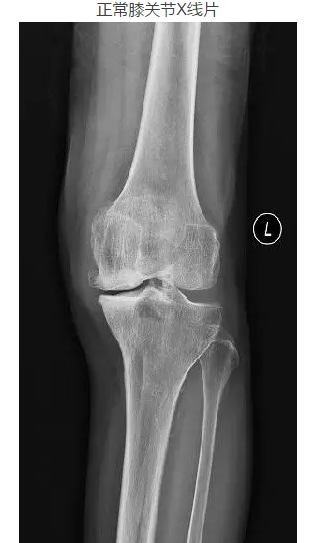

本病的X线表现主要以不同程度的关节间隙狭窄及关节内骨赘形成为特点,程度不同可有不同的分级。

膝骨性关节炎X线片